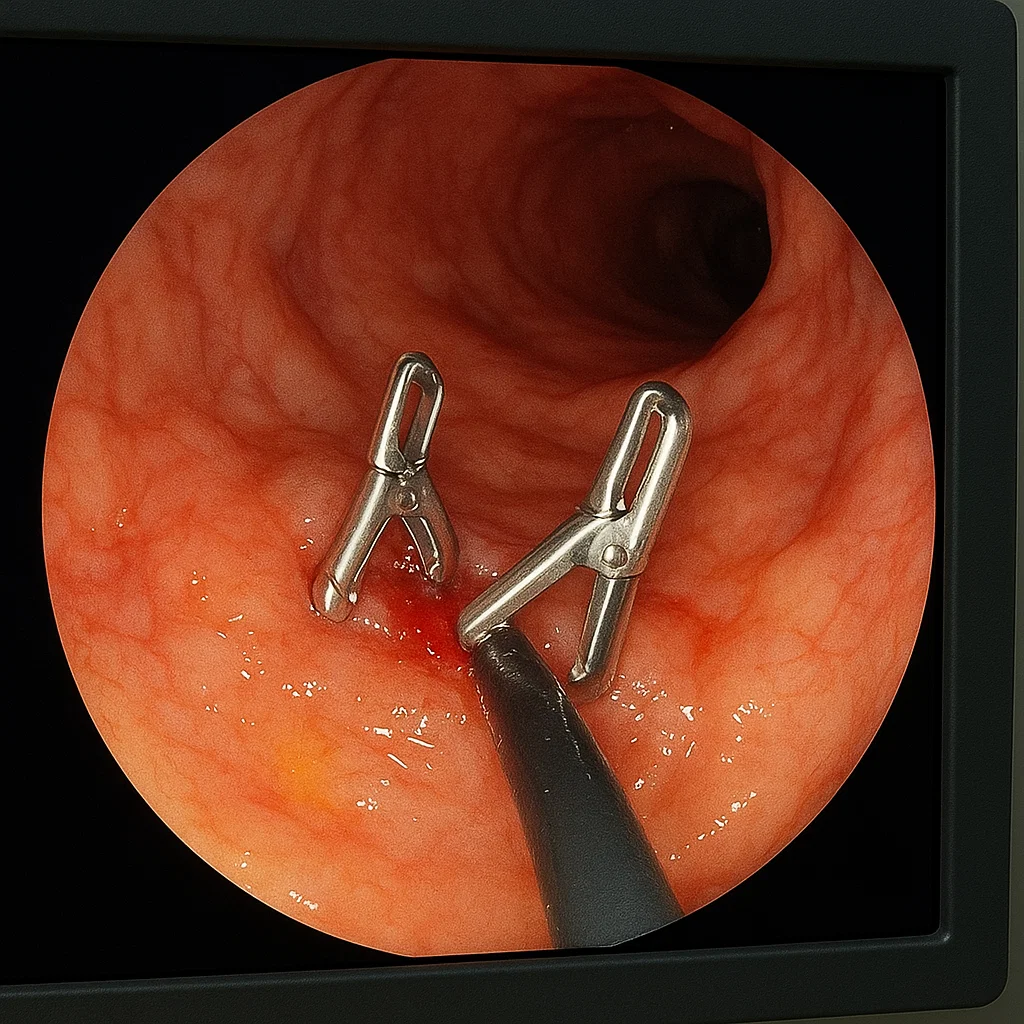

«Пульсирующая струя крови просто бьёт в 12-перстной кишке. Я нахожу источник, останавливаю клипсами, пациент жив, язва зарубцевалась — его выписали через несколько дней».

Это не операция в привычном смысле.

Это

операция через трубку, без разрезов, под контролем зрения. И если бы не гастроскопия, человек мог бы просто не дожить до утра.